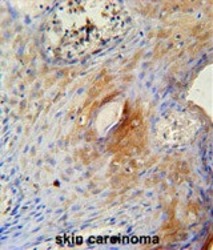

Supportive validation

- Submitted by

- Acris Antibodies GmbH (provider)

- Main image

- Experimental details

- TPRG1 Antibody (N-term) (AP54346PU-N) immunohistochemistry analysis in formalin fixed and paraffin embedded human skin carcinoma followed by peroxidase conjugation of the secondary antibody and DAB staining. This data demonstrates the use of the TPRG1 Antibody (N-term) for immunohistochemistry. Clinical relevance has not been evaluated.